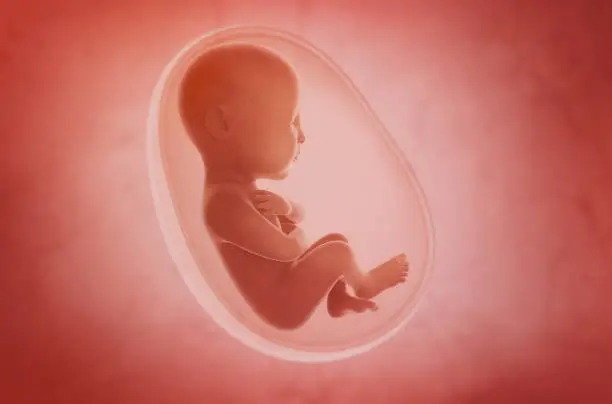

착상혈은 배란 후 수정된 난자가 자궁 내벽에 착상하는 과정에서 발생할 수 있는 출혈로, 이는 보통 배란 후 6일에서 12일 사이에 나타납니다. 수정란이 자궁벽에 자리 잡는 과정에서 자궁 내막의 일부가 손상되면서 소량의 출혈이 발생하게 되는 것입니다. 이 출혈은 보통 연한 분홍색이나 갈색을 띠고, 매우 가벼운 양으로 나타나며 길게는 며칠 정도 지속될 수 있습니다. 하지만 모든 여성들이 착상혈을 경험하는 것은 아니며, 개인에 따라 착상혈의 양상은 매우 다양하게 나타날 수 있습니다.

착상혈 외에도 임신 초기에는 다양한 신체 변화가 나타날 수 있습니다. 가슴의 통증이나 민감함, 피로감, 메스꺼움, 그리고 미열과 같은 증상들이 있을 수 있으며, 이는 착상이 이루어지고 임신 호르몬이 증가하는 과정에서 발생합니다. 이러한 증상들은 착상혈과 함께 나타날 수 있으며, 임신 초기 징후로 여겨질 수 있습니다. 그러나 이러한 증상들은 개인마다 다르게 나타나기 때문에 반드시 임신을 의미하지는 않습니다.